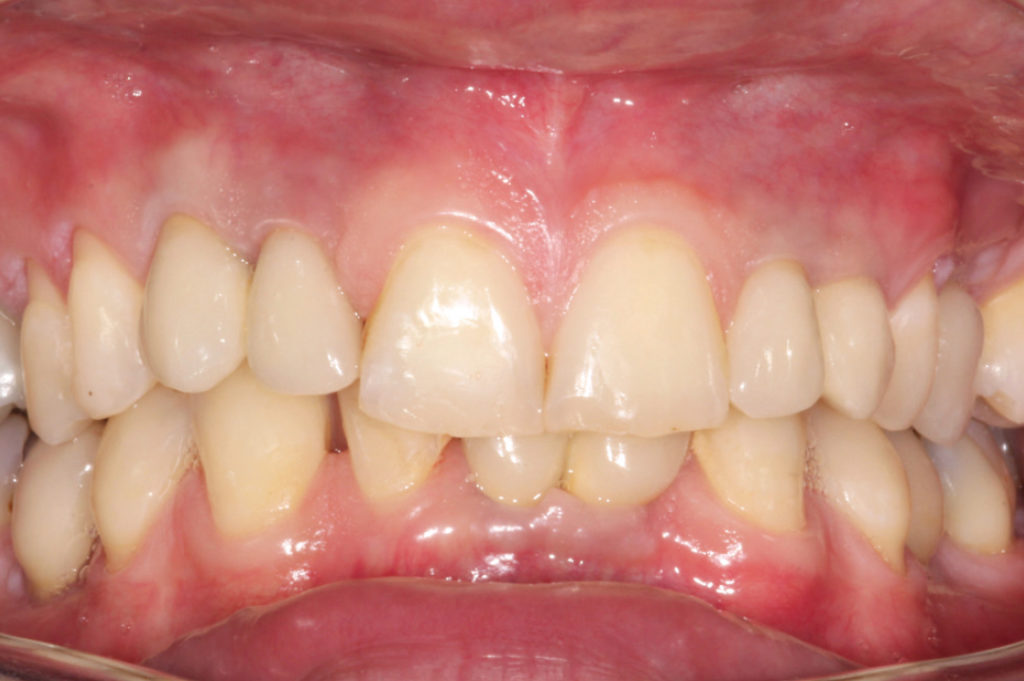

Situación clínica después del tratamiento ortodóntico

Situación clínica en julio 2017. Obsérvese la mucosa periimplantaria sana e intacta

Vista de los dientes #13 y #12 ocho años después de la inserción

Vista de los dientes #22 y #23 ocho años después de la inserción